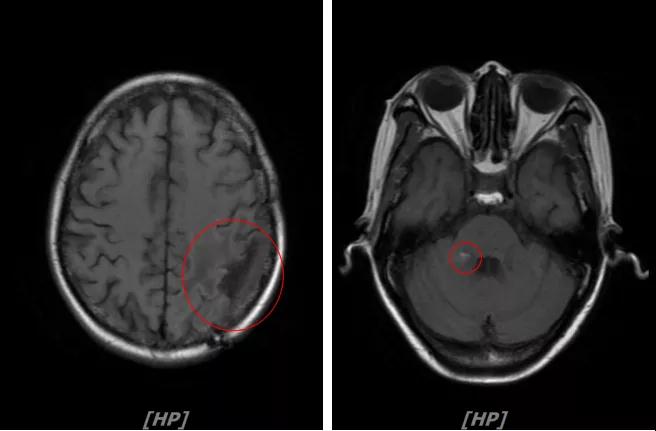

头颅增强MR:左侧顶枕叶见片状T1WI低信号、T2WI高信号影,增强后病灶边缘见局部斑片状强化改变,邻近脑膜轻度强化改变;右侧脑室三角区内侧见大小约8x14mm的结节影,T1WI低信号、T2WI等高信号,增强明显强化,灶周水肿明显;两侧脑室旁见片状异常信号,T1WI低信号,T2WI高信号,增强未见明显强化,余脑室、脑池、脑沟大小形态可,中线结构居中无移位

左顶叶脑转移瘤术后放疗后,左顶叶术区边缘强化灶;考虑肿瘤复发

右侧脑室三角区内侧转移瘤

两侧脑室旁云絮状异常信号,考虑放疗后改变